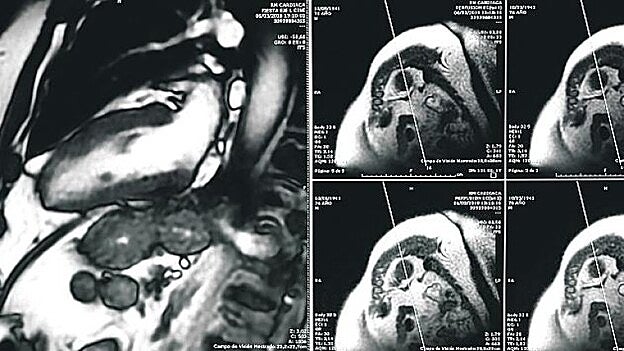

Hospitales San Roque es pionero en disponer de una unidad específica de Diagnóstico por la Imagen en Cardiología, lo que le permite lograr mejores resultados tanto diagnósticos, como terapéuticos y económicos.

Pero además, destaca, cuentan con la última tecnología lo que les permite «ampliar las fronteras en el diagnóstico más preciso de patologías cardíacas». Así, los pacientes podrán acceder en la Unidad de Imagen Cardíaca de Hospitales San Roque a un variado catálogo de pruebas de diagnóstico como la resonancia magnética cardíaca, una técnica libre de radiaciones ionizantes que permite la visualización con alta resolución del corazón y es el «gold estándar» para realizar el cálculo de función cardíaca. O la novedosa aplicación de T1 mapping, una técnica cada vez más en auge y que permite disponer de un método que podría apoyar al diagnóstico de diferentes patologías miocárdicas sin necesidad de la utilización de contraste con gadolinio.

Por otro lado, Hospitales San Roque es el único hospital en el que se hace resonancia cardíaca de estrés, una prueba que se utiliza cada vez más para el diagnóstico y la valoración de la isquemia y la viabilidad miocárdicas, y proporciona una evaluación segura y efectiva de los pacientes con enfermedad coronaria. La unidad de cardiología de Hospitales San Roque cuenta con un TAC Multidetector Coronario, un escáner que permite la visualización con alta resolución de las arterias del corazón de forma no invasiva. Gracias al avance tecnológico de esta máquina se puede realizar un estudio de coronarias con muy poca radiación y menos contraste iodado de lo que se usaba en el pasado.